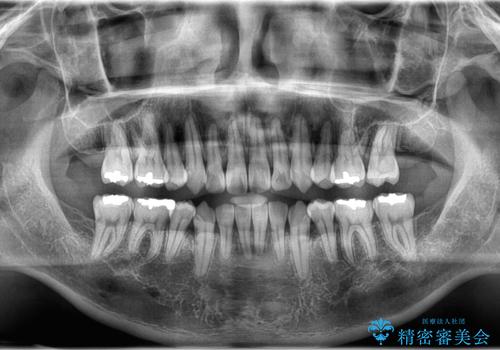

正面から見たときに右上2が全く見えないくらい、右上2が後ろに引っ込んでいる状態でしたが綺麗に並べる事が出来ました。

笑った時のスマイルラインもかなり綺麗になり大変ご満足いただく事が出来ました。

スムーズに治療を進める事ができ、2年2か月で治療をお終えました。

顔貌に対して歯の正中も合いました。